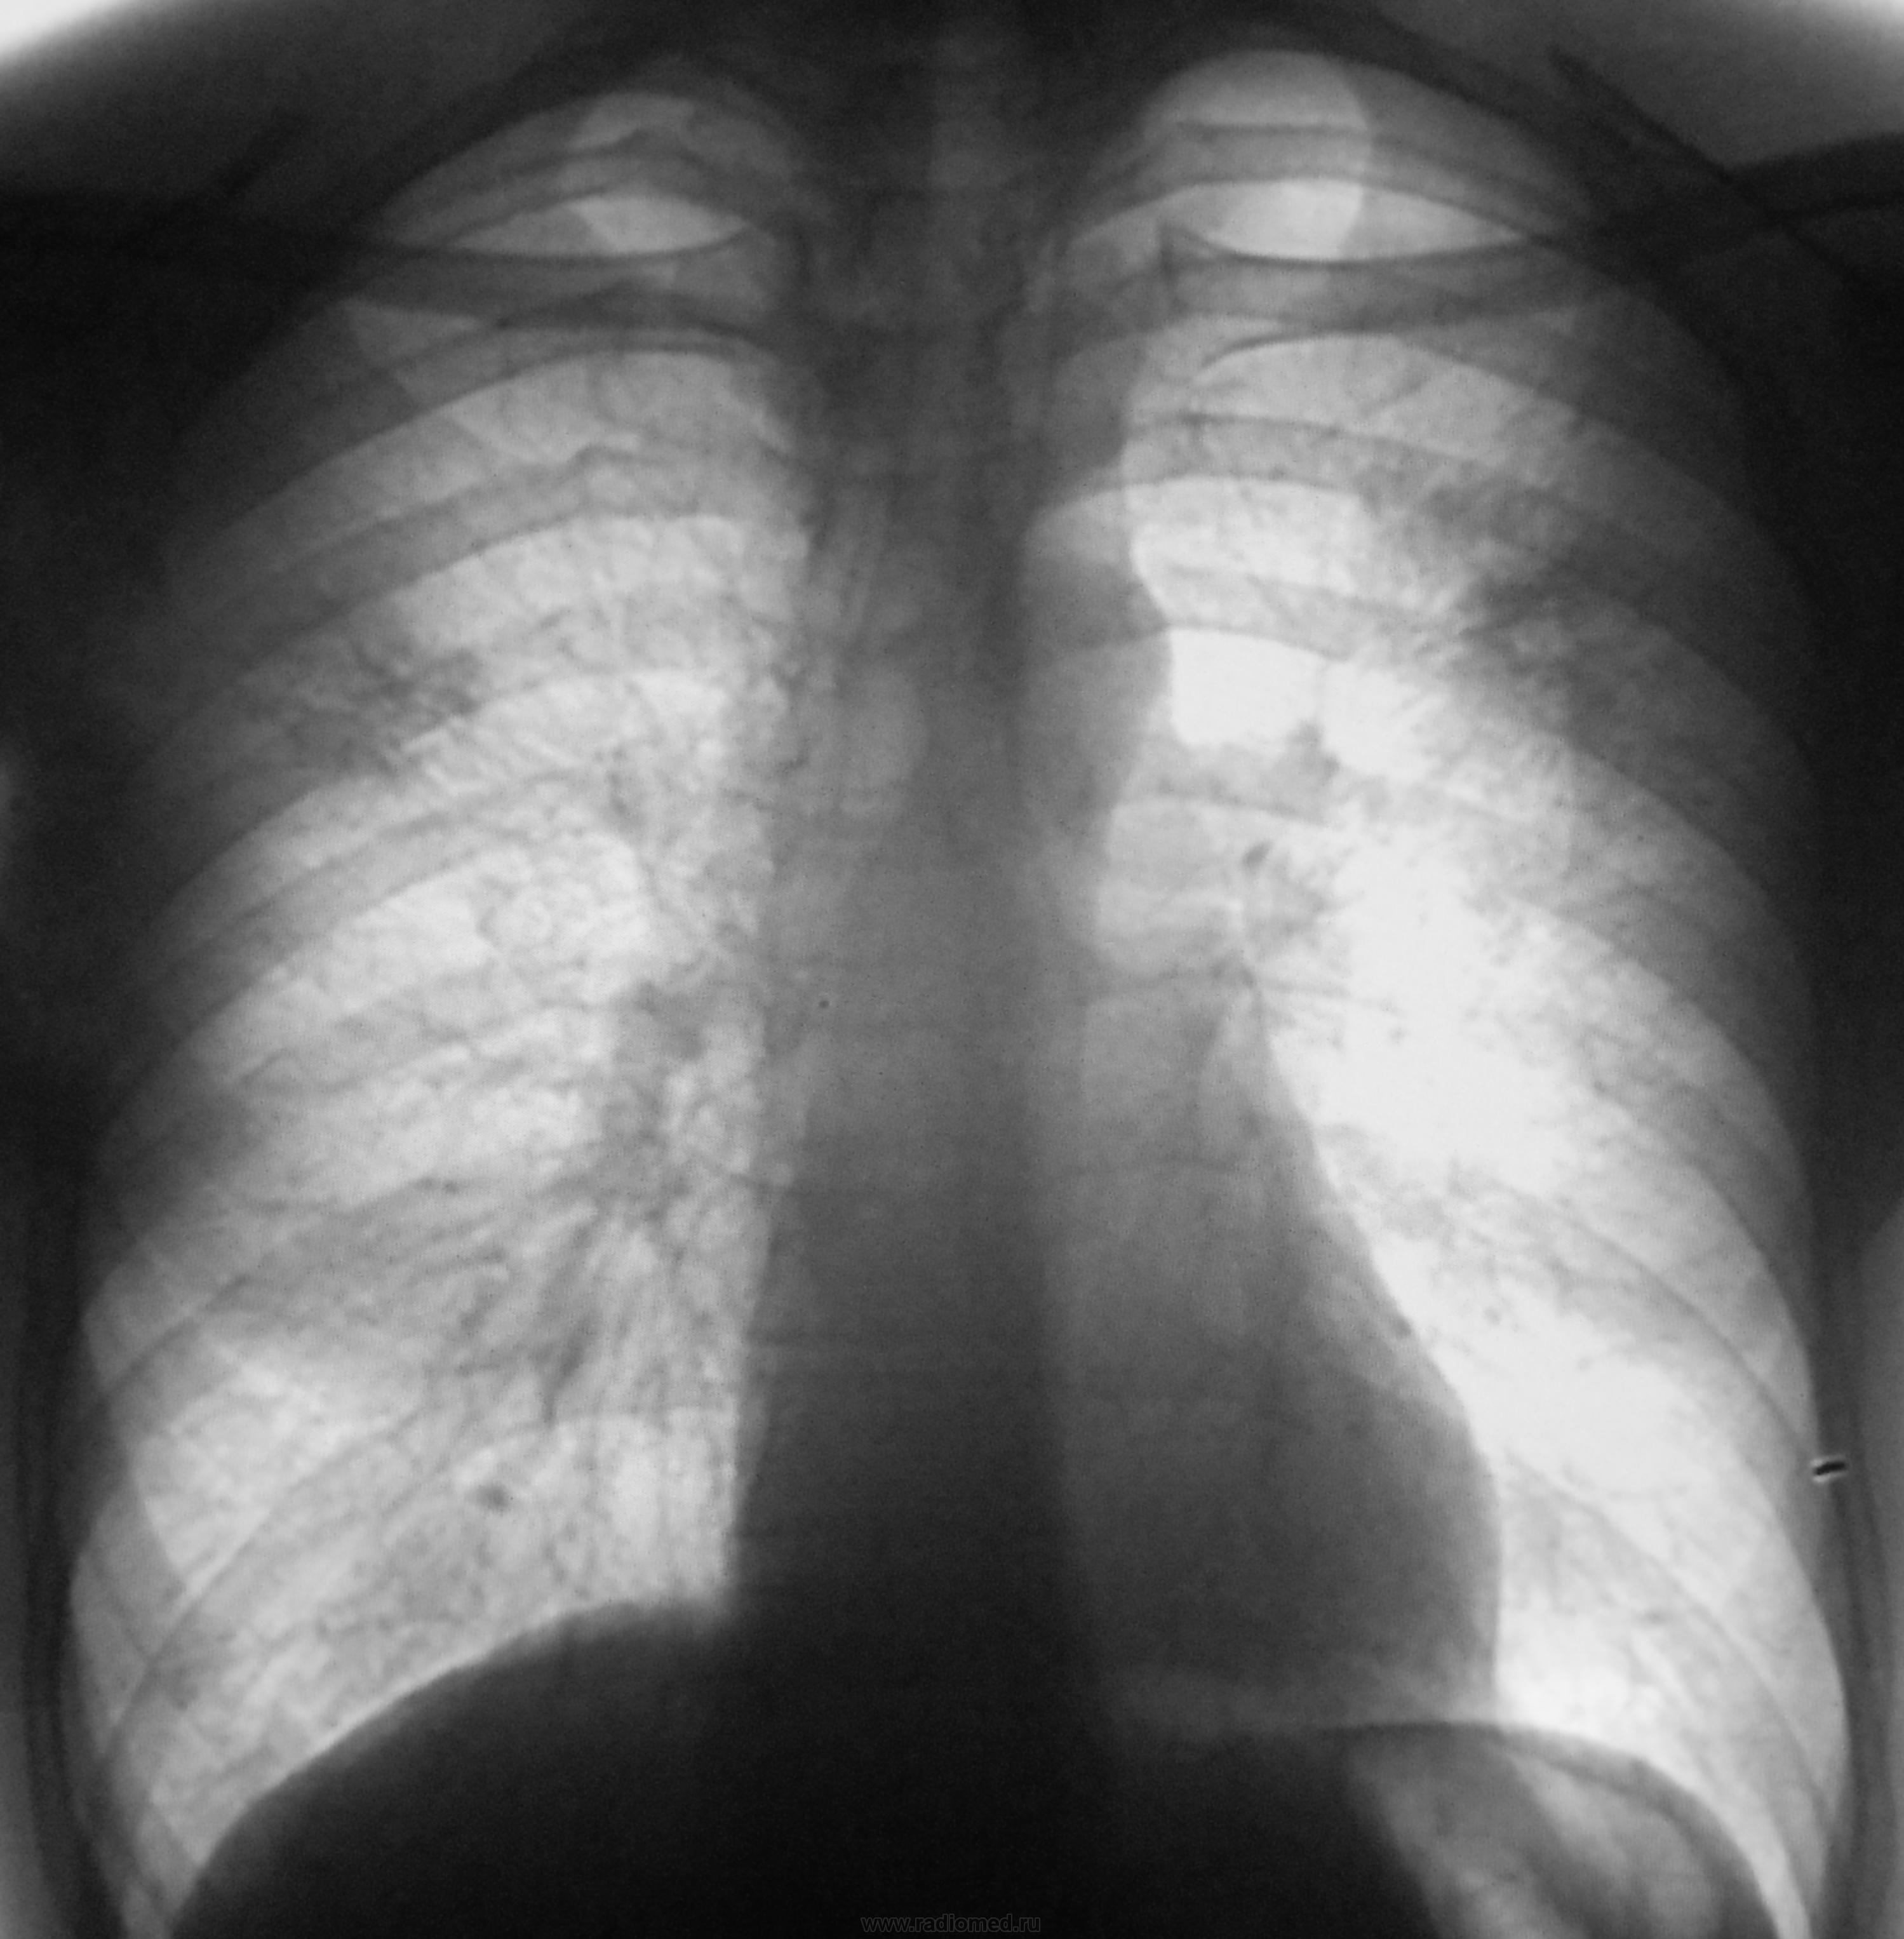

Я бы направила к фтизиатру с предв.диагнозом:инфильтративный туберкулез в/д об/легких в фазе распада.Можно,конечно и полечить АБ,но думаю,только время терять.ПТД и тмг сделают,и полечат,если сочтут нужным.

Неспокойно на верхушках.Левый корень плохо видно.Переснять бы на большом аппарате+левый бок.

Не успе разглядеть томограммы.Да к фтизиатру.

Томограммы.